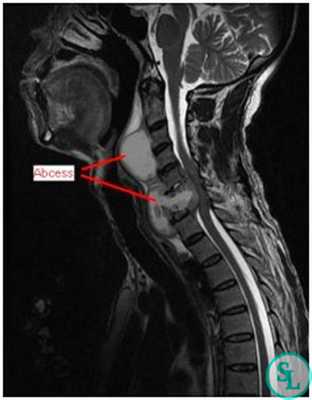

- МРТ позвоночника. Определяется снижение интенсивности сигнала на Т1-взвешенных снимках и его повышение на Т2-взвешенных изображениях, деформация межпозвоночных дисков, структурные изменения тел позвонков. Чувствительность магнитно-резонансной томографии достигает 96%, точность – 94%, поэтому ее считают «золотым стандартом» диагностики.

В диагностике заболеваний позвоночника большей популярностью пользуется магнитно-резонансная томография (или точнее «ядерно-магнитно-резонансная»), более безопасная и чувствительная, чем жесткое рентгеновское излучение. На снимках костные структуры получаются черными, но мягкие ткани, наполненные водой, передают все оттенки серого и белого цветов. Это позволяет обнаруживать мельчайшие объекты (узелковые образования, инфильтрации) и отслеживать динамику развития абсцесса.